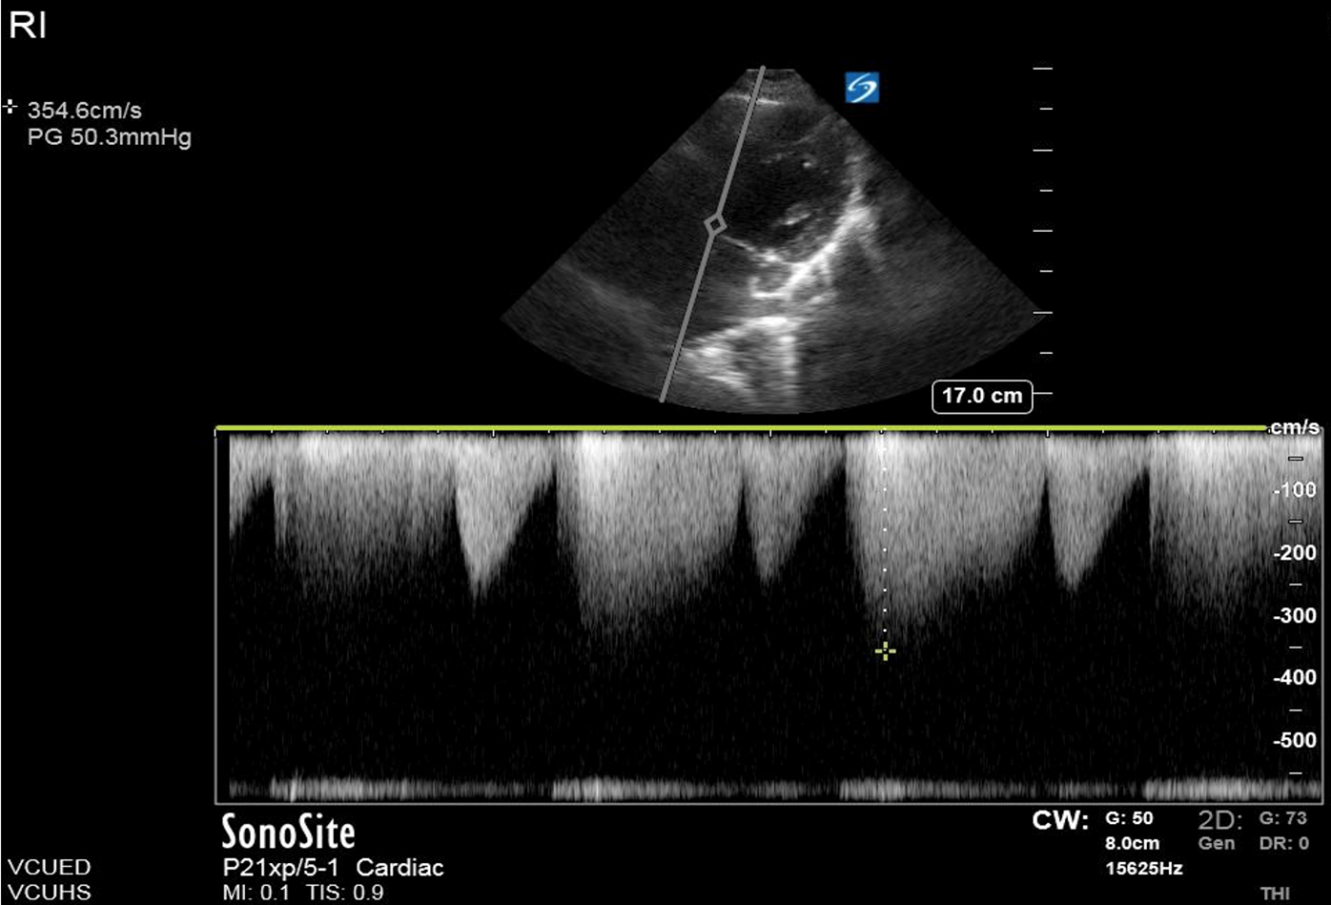

His initial vital signs showed a temperature of 36.9° C, BP 138/90, HR 82 and SpO2 99% on room air. His physical exam demonstrated a well-appearing man in no acute distress. His lungs were clear, his heartbeat was regular, but a systolic ejection murmur was appreciated. When questioned further he did not recall ever being told he has a heart murmur. Initial lab work in the ED showed no acute abnormality. His ECG was interpreted as non-ischemic with signs of left ventricular hypertrophy. His chest X-ray showed mild cardiomegaly but otherwise no acute cardiopulmonary process. A point-of-care echocardiogram (echo) revealed left ventricular hypertrophy and severe aortic stenosis. The images of this patient’s bedside echo were not saved, but an example of moderate aortic stenosis on an apical 5 chamber (A5C) view are demonstrated using continuous wave (CW) Doppler over the left ventricular outflow tract (figure 1).

Point-of-care echo should focus on the overall dynamics of the left side of the heart, as well as quantitative measures of the left ventricle and left ventricular outflow tract. Initial assessment in parasternal long axis (PSLx), parasternal short axis (PSSx) and A5C will elucidate general heart function as well as evaluate the aortic valve (AV) for number of leaflets, thickness, mobility, and calcification.7 Quantitative measurements of aortic stenosis should include Peak Aortic Velocity (>400cm/s = severe aortic stenosis), Mean Transaortic Gradient (<40mmHg = severe aortic stenosis) and Aortic Valve Area (<1cm² = severe aortic stenosis).8 It is important to interpret these measurements with the clinical context of the patient because the severity of stenosis may be significant for one patient but less significant for another.8 An intercurrent illness can affect the cardiac output and influence the velocity and pressure gradients across the AV.8

Figure 1. A patient with moderate aortic stenosis and peak aortic velocity at 354 cm/s.